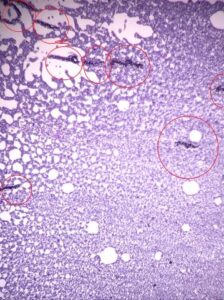

こんにちは(^_^)   寄生虫学の授業で生きているミクロフィラリアの観察をしました。   先ずはフィラリアとミクロフィラリアについて学びます。   今回は直接血液をスライドガラスに垂らして観察する直接法と塗抹をひいて染色した方法で観察しました。   直接法では動いているミクロフィラリアを観察できました(*^∪^*) うねうねと血液の中を動いているミクロフィラリアを観察した学生達は、思っていたよりも動きが速かったのと数が多かったことに驚いていました!! 残念ながら写真だとわからなかったです、、、。   こちらは染色したミクロフィラリアです。(赤丸の中にミクロフィラリアがいます)   今はフィラリア薬を飲んで駆虫している家庭が多いので、生きているミクロフィラリアを見られる機会はなかなかないです。 東京都・神奈川県の動物病院で働いている動物看護師さんの中では、生きているミクロフィラリアを観察したことがない人もいるみたいです。 そのため今回、生きているミクロフィラリアを観察できたのはとても貴重な体験でした!!   今後飼い主さんにフィラリアについて説明するときは、今回のことを思い出して説明してあげてください(^_^)v   ↓↓クリックお願いします